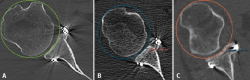

Figure 1. Estimation of glenoid axis and height according to the method of Barth(13). Two circumferences are traced: one lower, taking the posteroinferior glenoid border as reference, and one higher than the other and tangential to the glenoid borders. The line joining the centre of both circumferences is taken to represent the axis of the glenoid cavity. Over this, the height corresponding to half of the glenoid cavity and to 25% is established.

Taking the posteroinferior glenoid border as reference, we traced a first circumference over its contour, and a second circumference above the previous one and tangential to the glenoid borders. The line joining the centre of both circumferences was taken to represent the axis of the glenoid cavity. Over this we estimated the point corresponding to the half and 25% of the glenoid height (Figure 1). The sagittal section was used to determine the position of the graft in the craniocaudal direction (Figure 2). The length (in mm) of the bone defect was measured (B), along with the amount of bone graft covering the defect (A). Percentage covering of the bone defect was estimated from the ratio between A and B. The graft was considered to be well positioned when the percentage coverage of the defect was at least 90%.

Figure 3. Evaluation of the graft position in the axial view, according to the description of Kany et al.(14). A circumference is traced over the glenoid border, and following the curvature of the latter, the amount of graft (in mm) extending beyond or failing to reach this line is measured. Image A shows the graft perfectly positioned, following the curvature of the glenoid concavity. Image B shows the graft medial with respect to the line. Image C shows the graft positioned too lateral.

The position of the graft in the mediolateral direction was evaluated in the axial sections corresponding to 50% and 25% of the glenoid height. For this purpose we used the curvature method described by Kany et al.(14); on the glenoid border and following its curvature, a circumference was traced and we quantified (in mm) the amount of defect that did not reach or surpassed that line at the point where the graft was closest to the native glenoid cavity (Figure 3). Optimum positioning of the graft was considered when the latter was located in line with the glenoid cavity, up to 3 mm lateral or up to 5 mm medial with respect to the glenoid joint border(14). Grafts protruding more than 3 mm were considered to be located lateral, while those located more than 5 mm medial to the glenoid joint surface were classified as being medial.